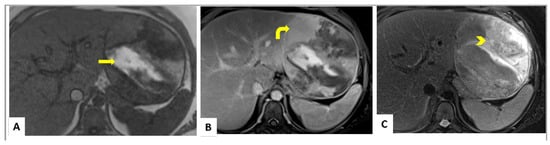

4. Imaging